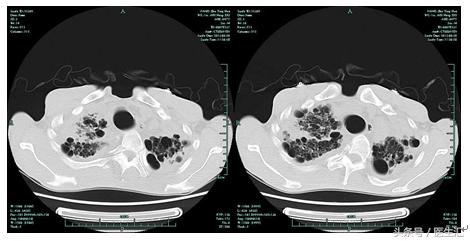

06-20肺CT平扫:

两肺间质性改变,肺气肿,两肺多发肺大泡。两肺上叶慢性感染机化。较2月12日CT大致相仿。

08-21增强扫描(一部位)):慢支、肺气肿伴两肺多发肺大泡;两肺间质性改变,左肺上叶病灶对比6月20日CT,部分病变有吸收好转。左上肺术后改变。两侧胸膜增厚粘连。